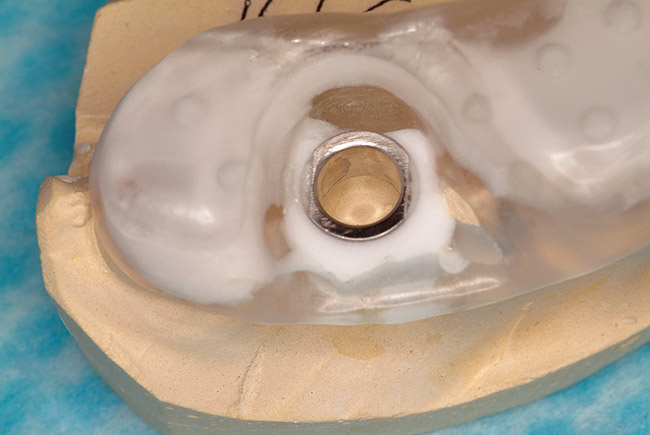

Figure 9: Stereolithic model of edentulous maxilla and bone-supported guided surgery stent.

Figure 9

These patients were tested for two different treatment options; either a bar-supported overdenture requiring four implants in the first premolar area or anterior to the bicuspids, or a "simple fixed prosthesis" anchored by six implants placed bilaterally from first-molar-to-first-molar regions. When a flapless, guided surgery was contemplated, the investigators determined that based on the available maxillary bone, 70% of patients (28 implants) could undergo this treatment modality. Of the 40 patients, 15% could not have any implants placed due to inadequate bone height and width. For "simple fixed prostheses," only 30% (72 implants) of patients presented with adequate bone dimensions permitting a flapless guided placement of six maxillary implants placed symmetrically around their arch in a flapless manner. For the fixed treatment, 18% of patients could not have any implants placed due in insufficient bone dimensions. The authors concluded that advertisement of computer-guided, flapless solutions are "euphoric," and tend to overlook patients' individual oral and anatomic conditions. They felt that guided surgery does provide better control of implant placement leading to higher predictability of treatment outcomes. In a study where the accuracy of virtually placed implants and actual positions in a cadaver model were compared, Petterson et al7 found significant differences related to deviations in hex, apex, and depth of the two placements. Without the preparedness to temper treatment expectations or plan on delivery of the pre-fabricated "final" prosthesis immediately after surgery, these types of studies should lead clinicians to proceed with caution in these procedures. The efficacy of an open approach, one requiring a mucoperiosteal flap, may be improved upon with a guided approach in cases where severe ridge-resorption is treated, and may be more predictably handled using this technology. A bone-supported template, affixed to the alveolar ridge with fixation screws, can be fabricated with numerous software package and stereolithography (Figure 8 and Figure 9). A full-thickness flap is elevated, exposing the resorbed alveolar ridge (Figure 10). Using osseous fixation screws, the template is stabilized to the ridge, preventing any movement during osteotomy preparation (Figure 11). Using a sleeve-in-sleeve, manufacturer-specific surgical armamentarium, implants can be placed in the optimal positions, where the maximum amount of initial bone to implant contact is achieved. The anticipated bone augmentation procedures can then be performed, which is not possible with a closed procedure (Figure 12). The flaps are subsequently closed, allowing for the patient to wear any transitional, soft-relined denture. The surgical guide can also serve an important function at the time of implant uncovering. The location of the implants beneath the healed mucosa can be determined by seating the guide and sounding with a 30-gauge anesthetic needle. Using a tissue punch, the implants can be uncovered without flap elevation; the cover screws can be removed and the appropriately sized healing abutments can be placed (Figure 13). From this point forward, traditional prosthetic steps are followed to fabricate an implant-supported/retained overdenture.